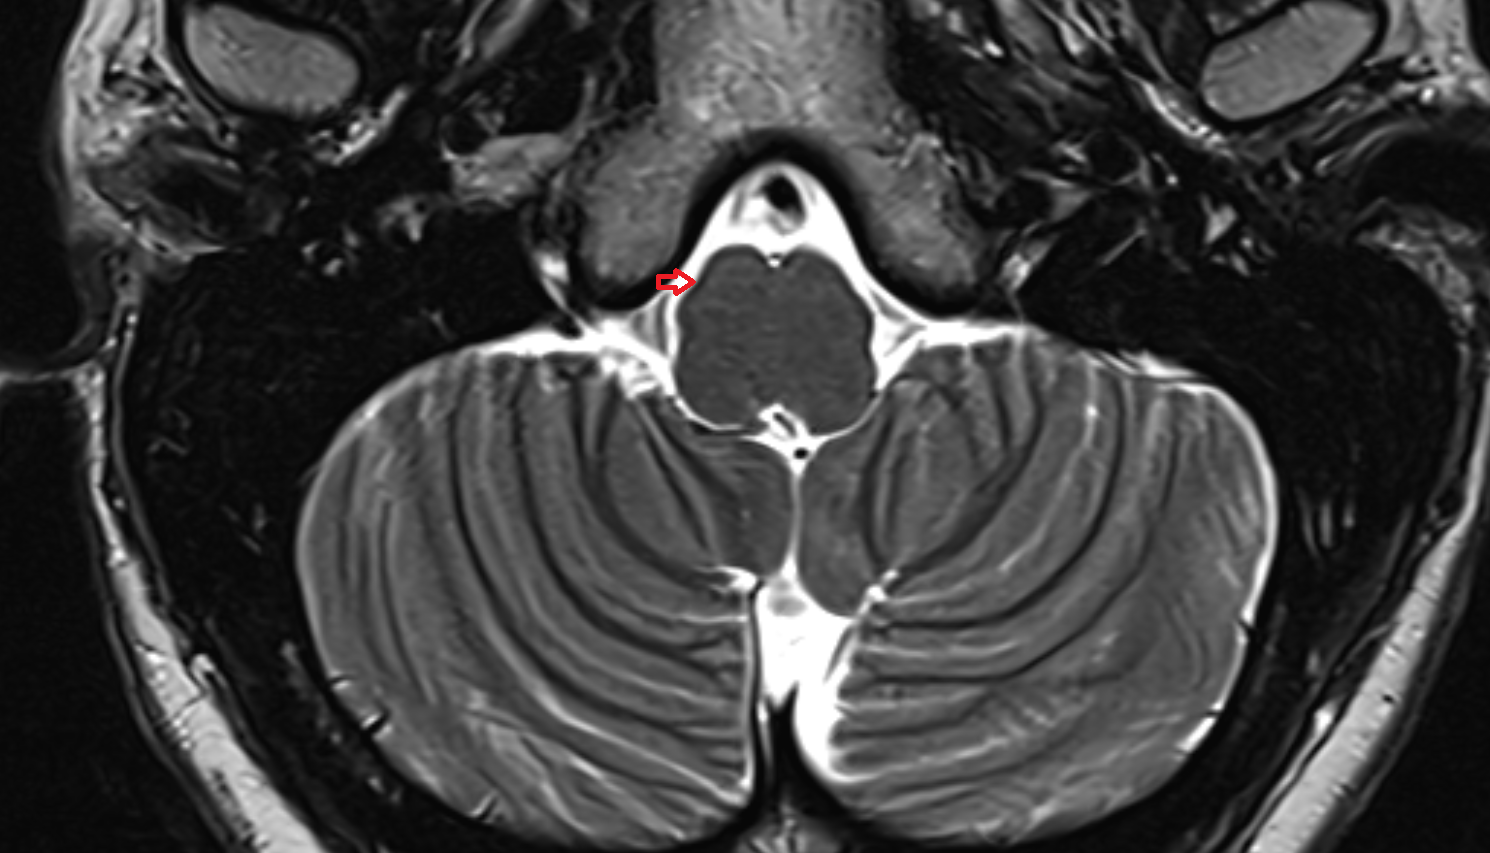

- Cerebellum

- Middle cerebellar peduncle